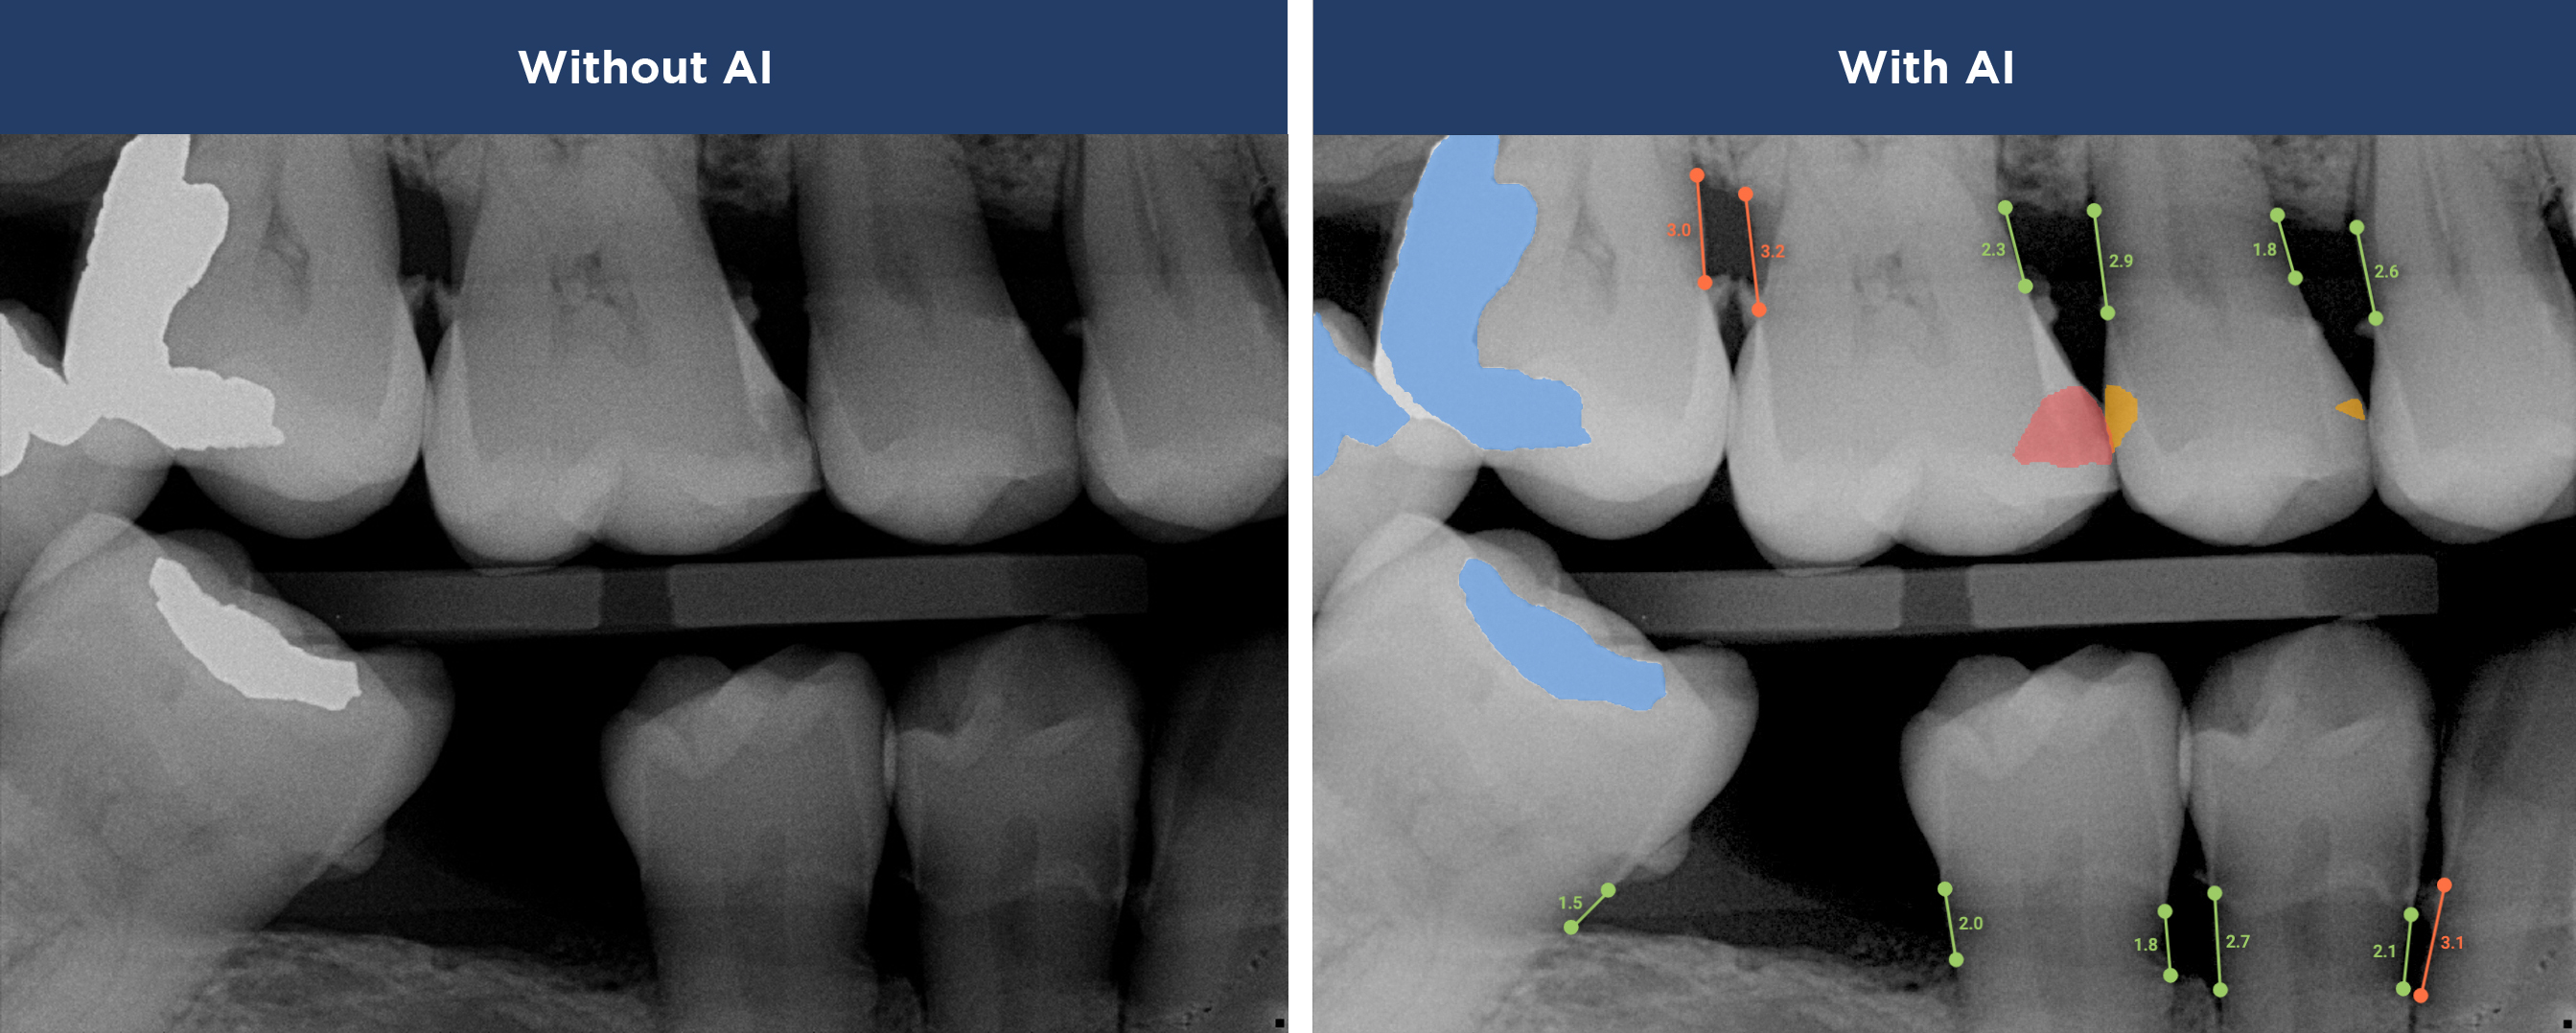

Overjet’s artificial intelligence technology transforms traditional black-and-white X-rays by adding a layer of data that instantly outlines decay (cavities) and measures bone loss. This makes it easy for you to see your results alongside your dentist. It’s like getting a second opinion delivered instantly. With Overjet’s analysis and easy-to-read presentation, you will have the information you need to make an informed decision about your oral health. Together, we’ll review your findings and discuss the best steps to take to achieve your goals.

Overjet’s artificial intelligence technology transforms traditional black-and-white X-rays by adding a layer of data that instantly outlines decay (cavities) and measures bone loss. This makes it easy for you to see your results alongside your dentist.